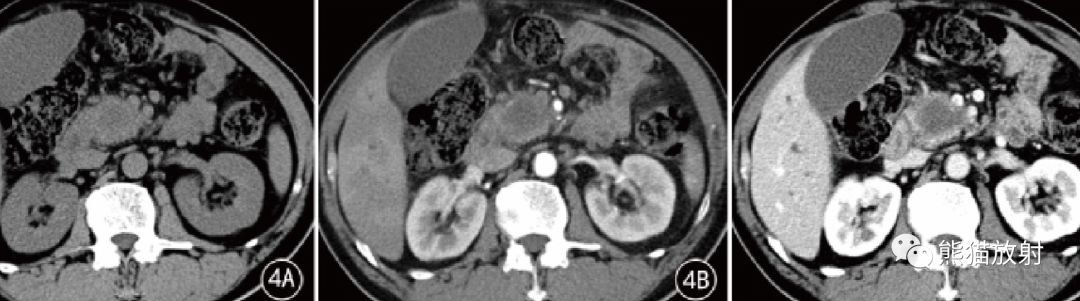

图4 男,65 岁。PDAC 胰头钩突部中分化导管腺癌。CT平扫显示略低密度肿块,增强扫描动脉期肿块轻度不均匀强化,门静脉期和延迟期渐进性强化不明显。冠状MPR示胰腺、尾部萎缩,胰管扩张,胆总管下端受侵、变窄,其上方胆内外胆管明显扩张。